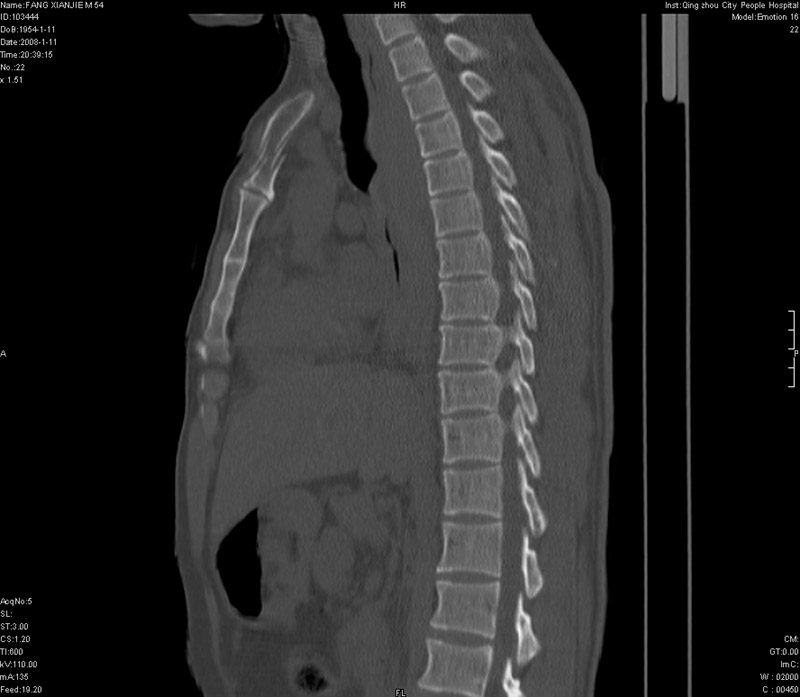

男性,40岁。胸部被车压伤伴胸痛1小时来院就诊。检查:一般情况尚可,血压110/80,胸部及上腹部压痛。结果在三天后公布。骨窗在横断位、冠矢状显示肋骨、胸椎、和胸骨未见骨折征象。

ct11308:胸部外伤1小时(证实病例) (2008-1-13 16:2)结果如下:病人入院后两小时后症状加重,8小时后在征得病人家属同意做了ct增强扫描。如下图。最终临床诊断:外伤性胸主动脉破裂并纵隔内血肿。由于有运动性伪影,胸骨在矢状面重建的图像似有骨折征,这是一种假象,我们称之为“假骨折”,这在多层ct重建中经常性遇到,必要时要结合横断图像鉴别之。现在,病人的一般情况较差,是否要手术家属尚有争议,如果手术修补,难度较大,需要专门预定制作固定支架。

以下是引用拾荒者在2008-1-16 18:46:00的发言:[br]ct11308:胸部外伤1小时(证实病例) (2008-1-13 16:2)结果如下:病人入院后两小时后症状加重,8小时后在征得病人家属同意做了ct增强扫描。如下图。最终临床诊断:外伤性胸主动脉破裂并纵隔内血肿。由于有运动性伪影,胸骨在矢状面重建的图像似有骨折征,这是一种假象,我们称之为“假骨折”,还有双侧肋骨的“假骨折”,这在多层ct重建中经常性遇到,必要时要结合横断图像鉴别之。现在,病人的一般情况较差,是否要手术家属尚有争议,如果手术修补,难度较大,需要专门预定制作固定支架。[br][br]再次表示感谢!

当然,对于该病例,其它非重要的诊断还有:右侧少量气胸;左侧胸腔积液;左侧轻度肺挫裂伤。对于纵隔内血肿,我们曾经遇到过多例,也有怀疑主动脉的破裂,但是,均未得到具体出血部位的明确诊断。